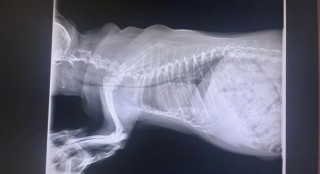

狗狗气管狭窄怎么办,(狗狗气管窄小)

狗狗气管塌陷吃什么药,狗狗气管塌陷吃什么药不疼?

狗狗气管狭窄怎么办,狗狗气管狭窄怎么办吃什么药?